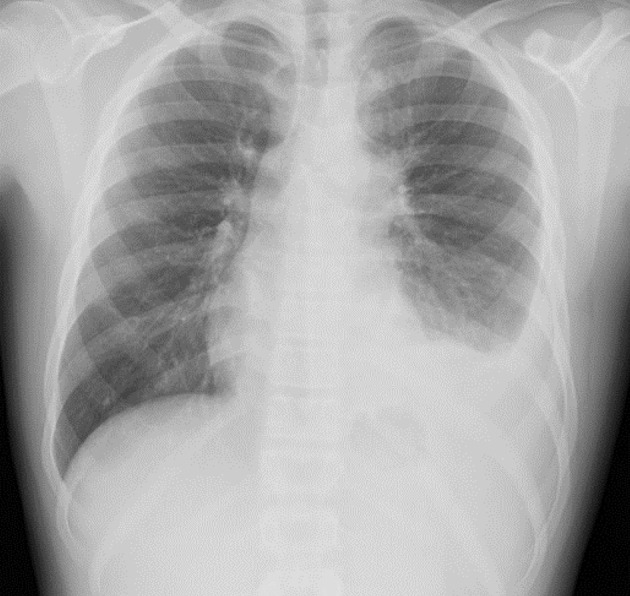

与真菌有关的原发性感染--组织胞浆菌病,在免疫功能正常的宿主中一般没有症状。胸片或计算机断层扫描成像等放射影像学检查可能会偶然发现钙化肉芽肿。不过,即使在免疫功能正常的宿主中,这些原发性感染偶尔也会导致包括呼吸系统损害在内的终末器官受累。对于出现呼吸道受累和纵隔腺病的患者,应将组织胞浆菌病列入鉴别诊断。我们介绍了两名因原发性组织胞浆菌感染导致纵隔和气管淋巴结病而出现肺部受累的儿童患者。第一例患者因胸腔积液导致呼吸困难,第二例患者因气管受压导致呼吸困难。本文介绍了荚膜组织胞浆菌的基本微生物学,介绍了以前有关原发性呼吸道受累的报道,并讨论了诊断和治疗方案。

Primary infection related to the fungus, histoplasmosis, is generally asymptomatic in immunocompetent hosts. Calcified granulomas may be noted incidentally on radiologic imaging such as chest radiographs or computed tomography imaging. However, even in immunocompetent hosts, these primary infections occasionally result in end-organ involvement including respiratory compromise. Histoplasmosis should be included in the differential diagnosis of patients presenting with respiratory involvement and mediastinal adenopathy. We present two pediatric-aged patients who developed pulmonary involvement related to a primary histoplasmosis infection that resulted in mediastinal and tracheal lymphadenopathy. These led to respiratory compromise due to pleural effusion in the first patient and tracheal compression in the second. In this paper, the basic microbiology of Histoplasma capsulatum is presented, previous reports of primary respiratory involvement presented, and diagnostic and therapeutic options discussed.